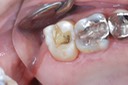

Photos of Clinical Operations

Mentors: Drs. Randy Allan, Greg Card, Peter Kearney

Clubs #44 and #50 joint meeting